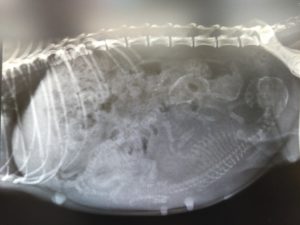

レントゲン検査

3頭の胎児を確認出来ました(・∀・)

体重は3kgを超え、ごはんもよく食べてくれます。このまま順調にお産を迎えられそうです。